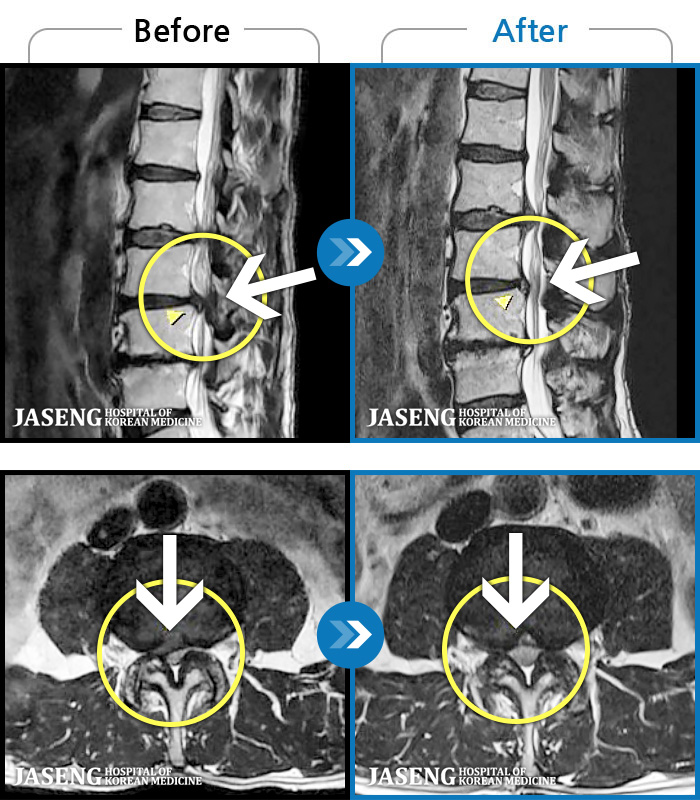

123 MRI ũ ʸ Ȯϼ.